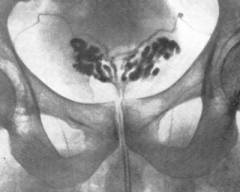

| 3. Везикулография | Метод для исключения туберкулеза или саркомы семенных пузырьков. Инвазивный: в семявыносящий проток вводят контрастное вещество (йодолипол, верографин) через разрез в мошонке. После вводится рентгенография. | При воспалении семенных пузырьков на рентгеновских снимках видно увеличение их размера, утолщение стенок и изменения рельефа. | |

| 4. Ультразвуковое исследование | Неинвазивный метод, использующий звуковые волны для выявления структурных изменений органа. | Ультразвуковые сканограммы показывают увеличенные и деформированные семенные пузырьки. | |